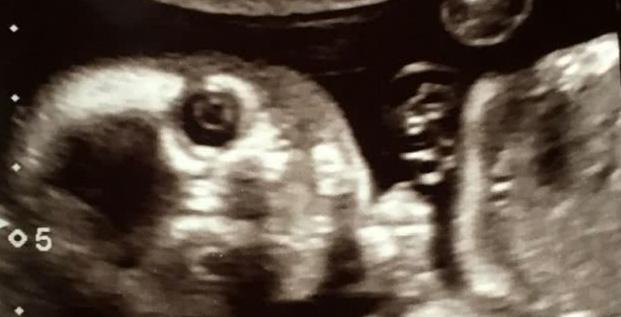

2月13日,英国《太阳报》登载了一张可爱的B超照片,照片中,小胎儿居然直视镜头,看起来像个小鬼般精灵可爱。

格里尔也是一位准妈妈,在做孕20周例行检查时,医生为胎儿做了B超扫描。

不过做B超时,医生和格里尔都吃了一惊,因为格里尔腹中的小宝宝突然转了一个位置,目光直视镜头,看起来很机灵、别具神采。医生说这样的情形是很罕见的。

做B超时,格里尔42岁的丈夫克林特·琼斯(Clint Jones)也在场,两人起初都觉得有点“恐怖”、有点震惊,但很快,两人都笑了起来。

格里尔将她宝宝的可爱B超照片发布在社交媒体上,配文说,大家都看过许多标准的、可爱的B超扫描照片,但她的宝宝照片有点罕见,非常有趣。